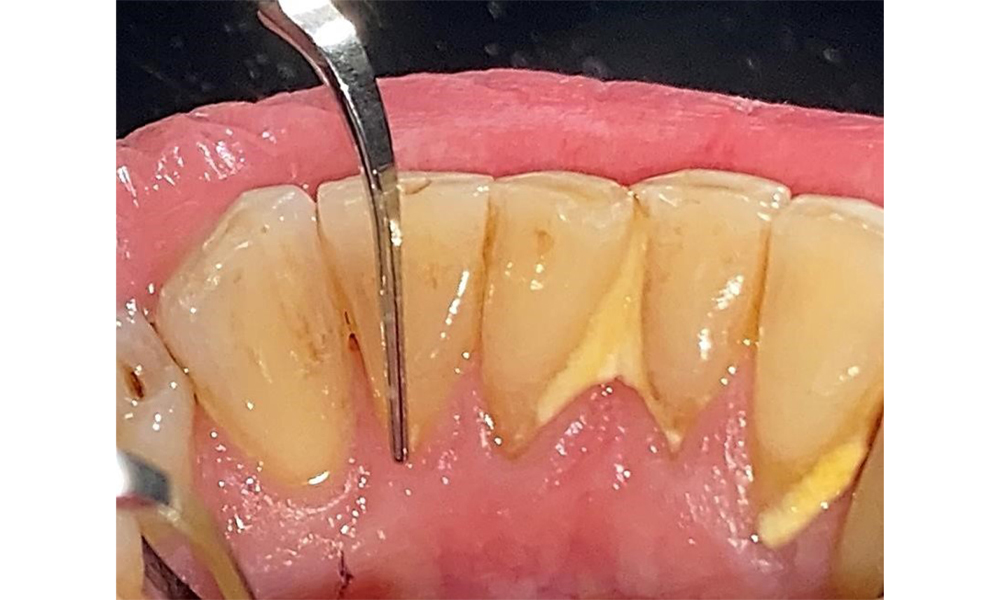

Ein ausführlicher Parodontalstatus mit Dokumentation der Taschentiefen, Blutung auf Sondierung, Rezessionen, Furkationsbefall, Lockerungsgrad ist 1x jährlich durchzuführen. So kann rechtzeitig auf eine mögliche Progression der parodontalen Vorerkrankung reagiert werden. Die Befundung der Zahnhartsubstanz und der Wurzeloberflächen ist ebenso notwendig, da das Risiko für Wurzelkaries durch die exponierten Wurzeloberflächen steigt.

IPC cycle icon: speech bubbles

Der Patient pflegt mit Interdentalbürstchen und mit einer elektrischen Zahnbürste. Er zeigt eine gute Compliance und ein gutes häusliches Mundhygieneverhalten bzw. - verständnis. Eine regelmäßige Motivation und Reinstruktion sind aufgrund des Progressionsrisikos unerlässlich insbesondere der Interdentalraumpflege aufgrund der erhöhten Sondierungstiefen in diesen Bereichen. Es zeigen sich lokalisiert Zahnstein in der Unterkieferfront lingual und weiche Beläge, die dem Patienten aufzuzeigen sind. Ggf. müssen Interdentalbürstchen auf die Größe geprüft und angepasst werden. Ein weicher Bürstenaufsatz ist aufgrund der freiliegenden Wurzeloberfläche zu empfehlen, um keilförmigen Defekten vorzubeugen. Eine Zahnpasta mit einem niedrig abrasiven Wert sollte angewendet werden.

In der Instrumentierung sind bezüglich der Methodenwahl keine Einschränkungen gegeben. Aufgrund der parodontalen Vorerkrankung und dem hohen Rezidivrisikos ist die Vorbeugung einer Erkrankungsprogression durch die regelmäßige supra- und subgingivale Instrumentierung unerlässlich. Die Wahl der Instrumente zur mechanischen Biofilmentfernung ist aus allgemeingesundheitlicher Sicht nicht eingeschränkt und erfolgt bedarfsgerecht. Harte und mineralisierte Beläge wie Zahnstein und Konkremente sind mittels Handinstrumenten oder Schall/ Ultraschallscalern zu entfernen (Abb. 9) (8, 9).